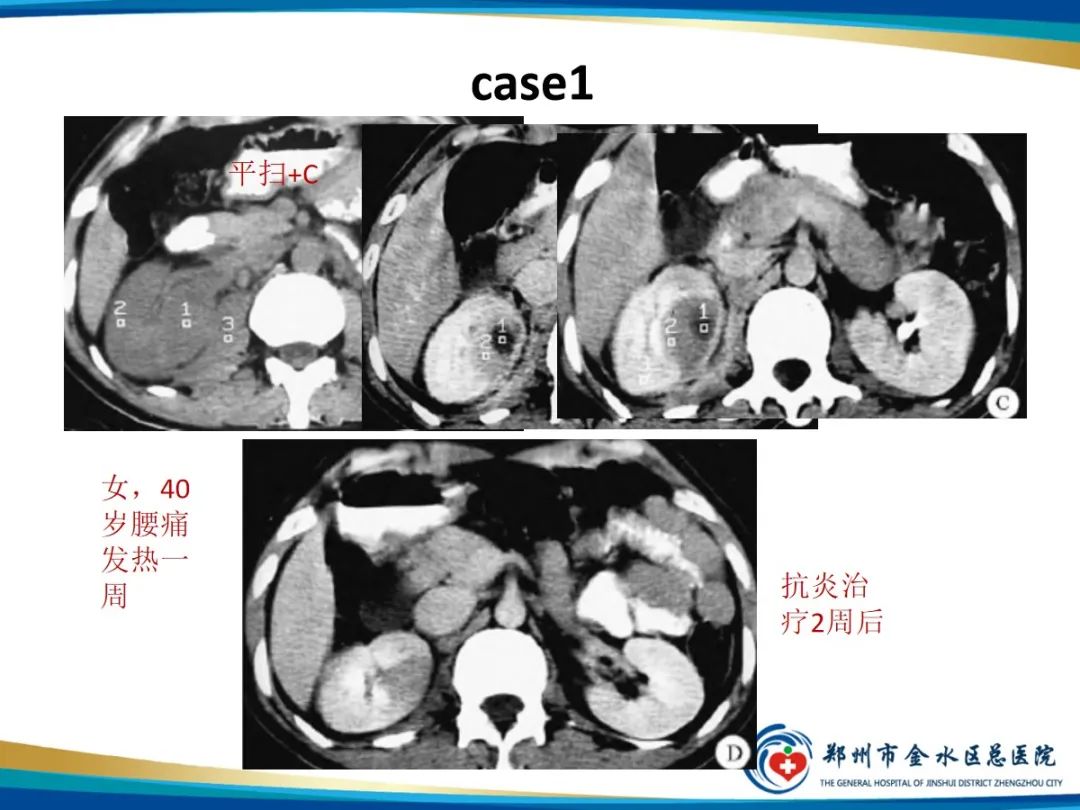

【PPT】肾细胞癌-1